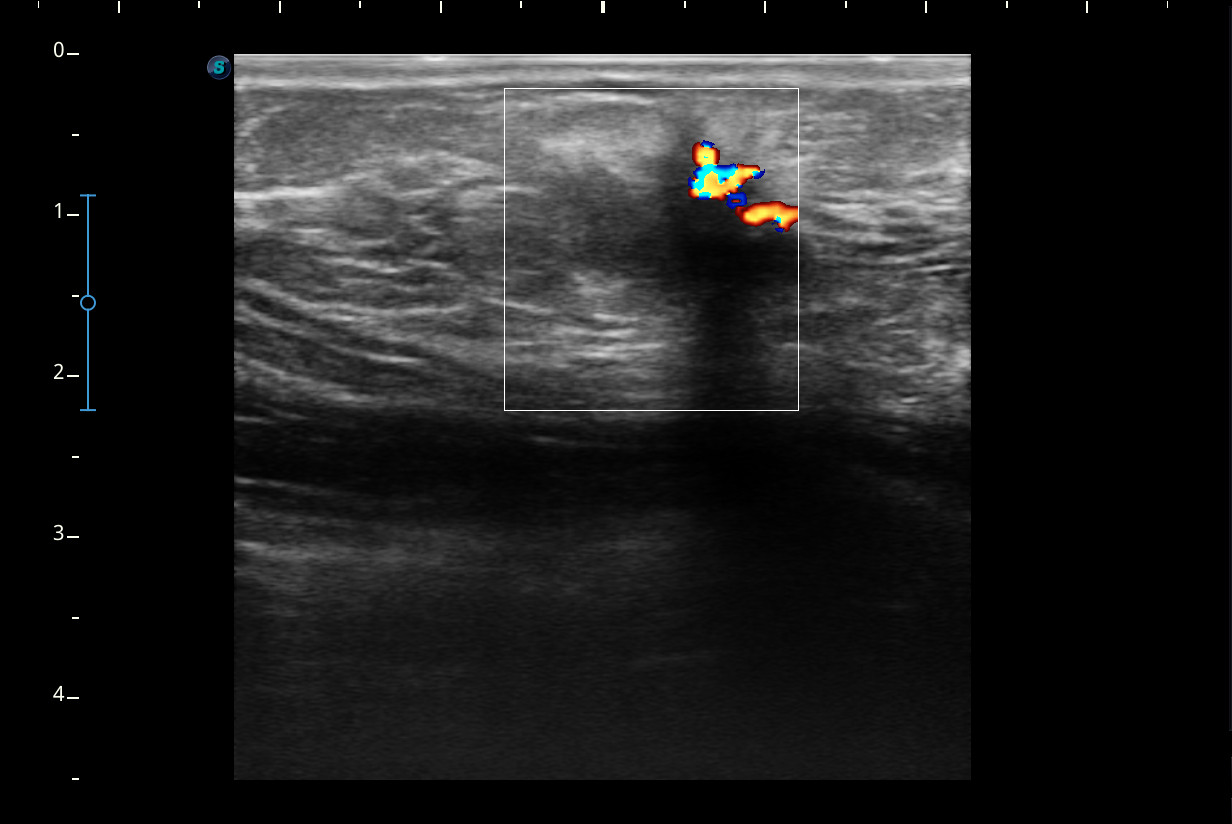

Hallazgos ecográficos

Se visualiza un nódulo mal delimitado, de bordes irregulares y algo espiculados, con captación doppler color sobre todo en periferia y posibles focos centrales de necrosis, compatible con posible neoplasia.